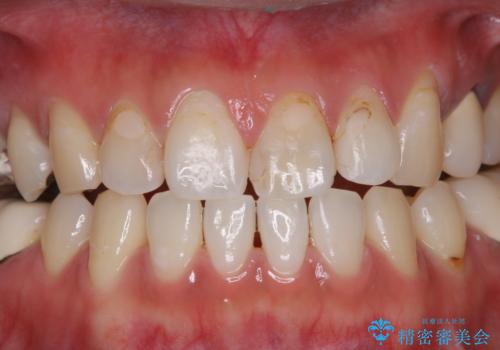

- 虫歯治療を始める前に、まずはしっかり汚れを取りたいとのことで来院されました。歯石やステインが分厚く付着していたため、PMTC60分コースを行いました。

歯の表面に、茶色く色が残っている所がありますが、これは詰め物の変色によるものです。以前に、CR(コンポジットレジン)による虫歯治療がされています。

CRは経年的劣化や、着色してしまうことがあります。PMTCでクリーニングを行うと、古いCRが目立つことがあるため、気になる際は詰め替えを行います。

茶色くなっている部分が、着色なのか、劣化なのか、虫歯によるものなのかは判別が難しいことがあります。そのため、定期的にPMTCを行うことで状態の確認が的確に行えます。